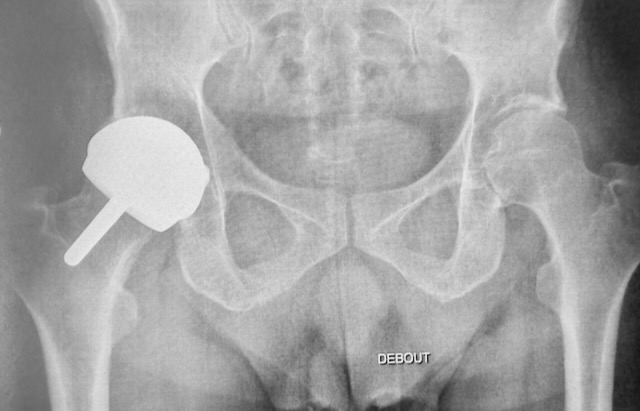

Venons-en au fait et à ce qui me motive à écrire aujourd’hui?! Il y a environ 15 ans (vers 2006) j’ai remarqué que les patients que j’opérais vers le mois de mars/avril avaient des suites plus longues que ceux que j’opérais en septembre octobre. J’ai demandé des dosages de vitamine D chez tous mes patients et là je suis tombé sur les fesses?! Les chiffres étaient simplement dramatiques. Les seules qui avaient des chiffres vaguement corrects étaient les femmes qui étaient suivies par un bon gynécologue. Depuis toute personne qui met un pied dans mon bureau repart avec une prescription pour au moins 4 mois de vitamine D. J’explique ensuite qu’il faut en prendre à vie l’hiver, mais là, j’ai bien l’impression de parler dans le vide.

Quand j’ai commencé à prescrire de la vitamine D à tout le monde, j’avais l’idée que cela favoriserait la fixation des prothèses au niveau de l’os, mais je n’avais pas du tout prévu que cela me débarrasserait des infections nosocomiales. Ces 10 dernières années, j’ai dû diviser par 10 le taux d’infection sur prothèse. Ça n’est probablement pas uniquement grâce à la vitamine D, mais quand même, ça doit jouer un rôle. Aucune infection sur prothèse primaire depuis 2015 à ma connaissance et la dernière que j’ai eue c’était juste un super obèse diabétique donc vraiment un patient à risque.